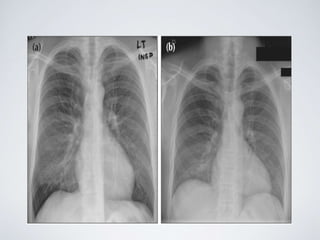

• #25 PA CXRs of the same patient taken minutes apart: (a) was obtained during a good inspiration, and (b) was obtained during a poor inspiration. In (b) the heart appears enlarged. A shallow inspiration can cause spurious cardiomegaly and also crowding of vessels at the lung bases. And can mimic infection.